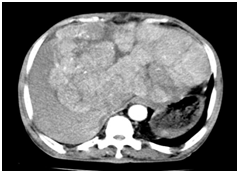

Abdominal CT scan was performed in 79 patients (34%). It was performed in conjunction with ultrasound in 71 patients (90%). There was hepatomegaly in 70 patients (88.6%). The nodules were noted in 76 cases (96.2%), with an average size of 98.9 mm (range 13 to 223 mm). The distribution of lesions according to the number of nodule and headquartered in CT is noted in Table 2. Early contrast enhancement during the arterial phase, with a washing portal phase was present in 61 cases (77.2%) Figure 2. These aspects were not specified in 16 cases (20.2%). The nodules were hypo‒vascular in 2 cases (2.6%). The effusion intraperitoneal was visualized in 30 cases (38%). The presence of a venous invasion was noted in 22 cases (27.8%). Deep adenomegalies were present in 9 cases (11.4%). The alpha‒fetoprotein levels were performed in 230 cases (88.1%). The rate was very suggestive in 174 cases (75.7%), reminiscent in 38 cases (16.5%) and negative in 18 cases (7.8%). Histological confirmation was performed in 44 cases (18.8%). Hepatocellular carcinomas (HCC) accounted for the majority of the lesions found in 42 cases (95.5%). Of these lesions, 33 were poorly differentiated, moderately differentiated 4 and 5 well differentiated. We also noted one case of fibro‒lamellar carcinoma and 1 case of cholangio carcinoma. The staging had identified 18 cases (8%) of lung metastases (13 cases of 37 chest X‒ray front and 5 cases of 7 chest CT).

Figure 2 Axial cuts in CT scan of liver.

1. Without contrast. Tissular heterogenous masse in the left liver isodense compared to the rest of the liver.

2. After contrast injection in arterial phase. The tumor is hypervascularized compared to the rest of the liver.

3. After contrast injection in venous phase. The tumor appears hypodense compared to the rest of the liver (wash out).